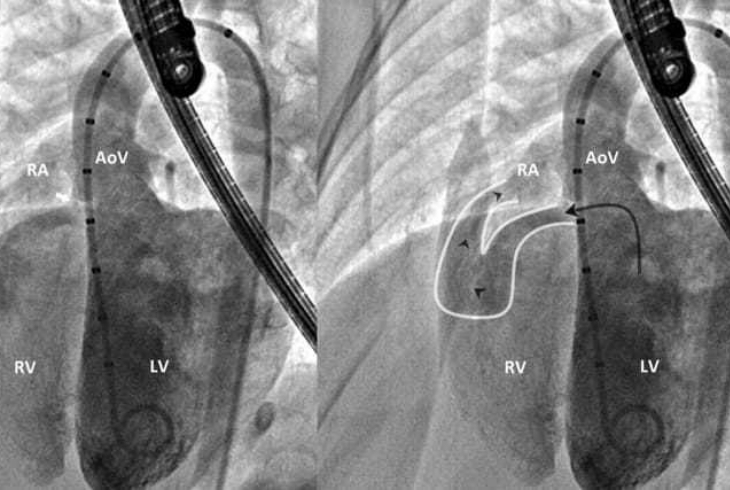

Diagnostic Catheterization & Angiography

A minimally invasive procedure using contrast dye and X-rays to assess heart chambers, vessels, and pressures for accurate diagnosis.

Balloon Atrial Septostomy

A life-saving procedure creating or enlarging an opening between heart’s upper chambers to improve oxygenation in critical congenital heart defects.